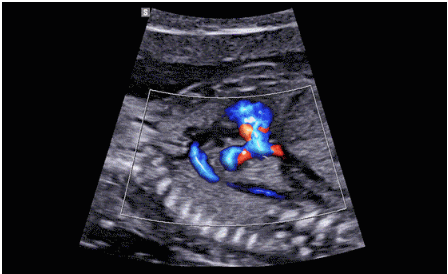

CrystalLive?是三星最新的超聲成像引擎,同時(shí)增強(qiáng)了2D圖像處理能力、3D渲染能力和彩色信號(hào)處理能力,能夠在復(fù)雜情況下提供出色的圖像性能,具備檢測(cè)外周血管、微循環(huán)血流的能力。